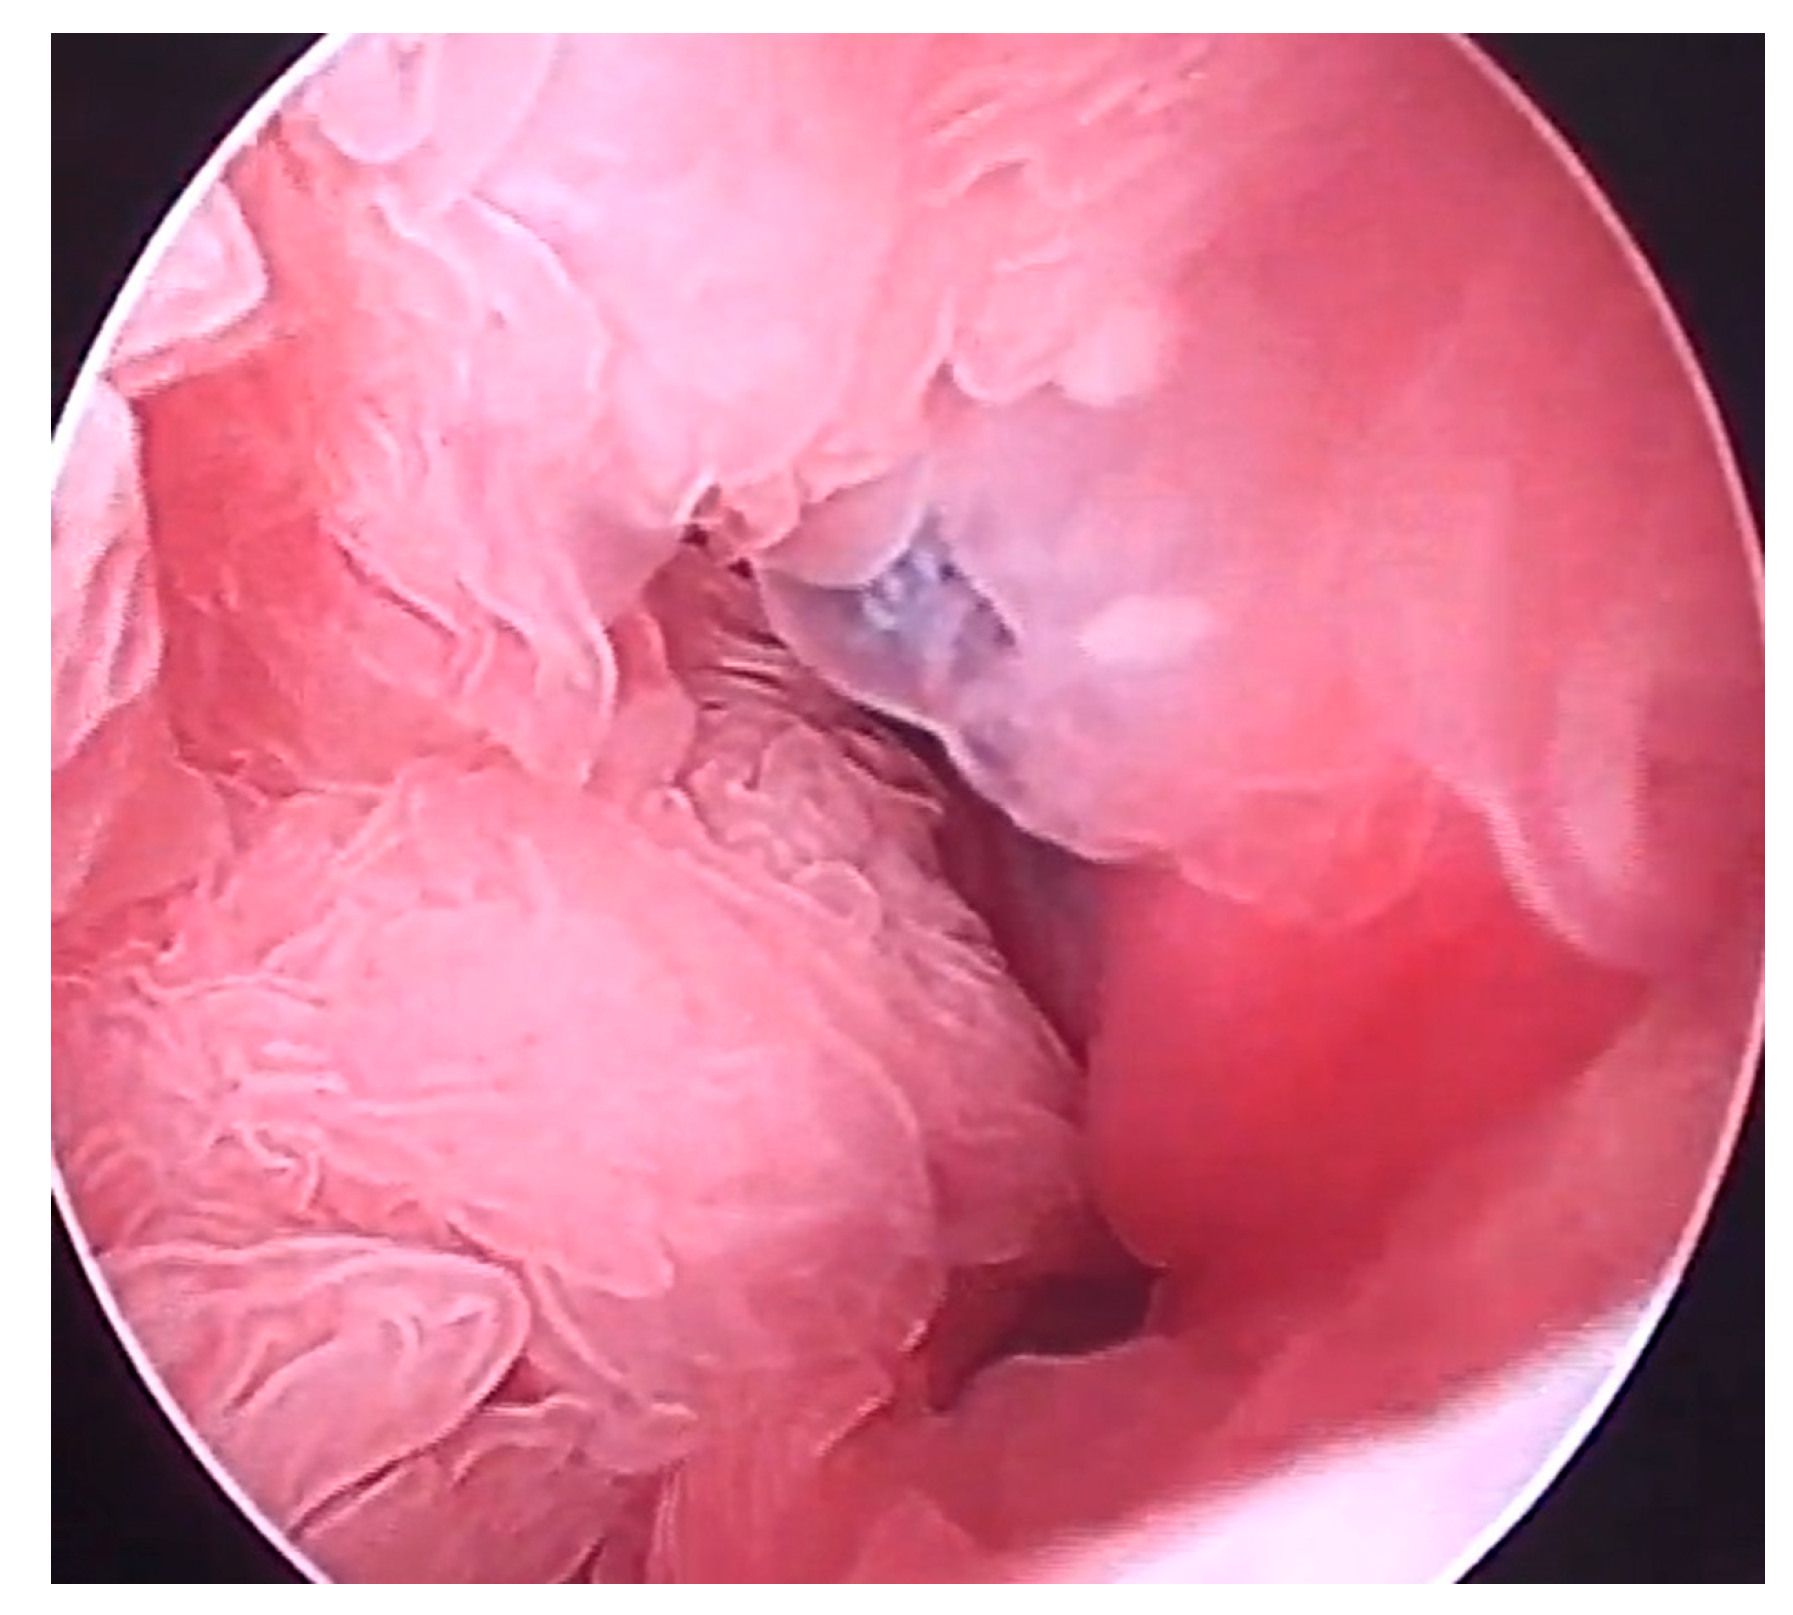

Hysteroscopy: Under the same anesthetic condition, the animal was subsequently examined by hysteroscopy using a gastroscope (Fujifilm EG 530NP; outer diameter 4.9 mm and working channel 2.0 mm, Fujifilm Co., Tokyo, Japan) and a video processor (TC200EN; KARL STORZ Endoscopy Japan K.K., Tokyo, Japan). Under endoscopic observation, while moving the introduced endoscope toward the deep areas of the uterine lumen, a large amount of clear fluid content without turbidity accumulation was seen within the uterine lumen. The corrugated thickening of the endometrium was observed throughout the uterine lumen (Figure 3). Water flushing from the endoscope into the uterine lumen appeared to float in the endometrial corrugations, suggesting softer structures. The endometrial surfaces were pale pink without discoloration. The corrugated structures were collected using biopsy forceps (2.0 mm × 1150 mm; Olympus FB-211D, Olympus Medical Systems Co., Tokyo, Japan) and introduced through a working channel.

Figure 3.

Hysteroscopic appearance of the uterus. Corrugation is evident in the whole area of the endometrial walls.

Hysteroscopy is routinely used for intrauterine catheterization and artificial insemination in goats [27,40]. In the present case, hysteroscopy was performed under deep anesthesia for CT examination before the procedure. Hysteroscopy has been performed in previously examined bovine, buffalo, equine, and caprine cases in their standing position, with or without sedation [27,28,29,30,41]. Epidural anesthesia is required when hysteroscopy is performed in unanesthetized animals [27,28,29,30]. The applicable diameters of endoscopes to be introduced into the uterine lumen of examined goats have ranged from 5.0 to 5.5 mm [10,30]. The smaller diameter of an endoscope (e.g., 2 mm) may be recommended for application in female caprine cases, based on a previous practical record wherein the intrauterine introduction of the larger diameter of the endoscope was faulty in 55.8% of uteri if incision in the cervix was not made [10,40]. The intrauterine infusions of sterile saline or lactated Ringer’s solution can lead to the distention of the uterine lumen, contributing to good endoscopic observations [30]. Flushing of the uterine lumen was performed in the same manner as in the present case, allowing for the observation of color and turbidity of the intrauterine effusion and subsequent cytological and bacteriological examinations, although the stirred mucopurulent materials could cause unclearness in the hysteroscopic view in the previous cases [30]. Endometritis is a common uterine disease for which hysteroscopy is preferred [10,29,30]. The previous use of hysteroscopy in sick female goats enabled the identification of endometritis in 45.2% of cases, followed by the detection of endometrial hemorrhages, hydrometra, mucometra, and pyometra in 19.4, 16.1, 9.9, and 9.7% cases, respectively [10]. The common hysteroscopic appearances of endometritis are the discoloration and thickening of the endometrial walls of the affected uterus, whereas ultrasonography enables the demonstration of only endometrial thickening [10,26,29]. Additionally, the corrugation of thickened endometrial walls can be commonly identified in hysteroscopic observations [29], similar to that in the present case. Hysteroscopy-assisted biopsy was successfully performed to identify endometritis preoperatively in the present case. Thus, this technique is the most optimal approach for hysteroscopy, which has also been performed in previous caprine cases [9,27,28]. Under hysteroscopic observations, biopsy specimens can be selectively collected from the pathological surface of the endometrium, identified based on discoloration and ulceration, using pilling biopsy forceps [16,17,41]. The hysteroscopic detection of endometritis can consequently contribute to the diagnosis of hydrometra because these uterine lesions mostly occur concurrently in affected female goats [9,10].